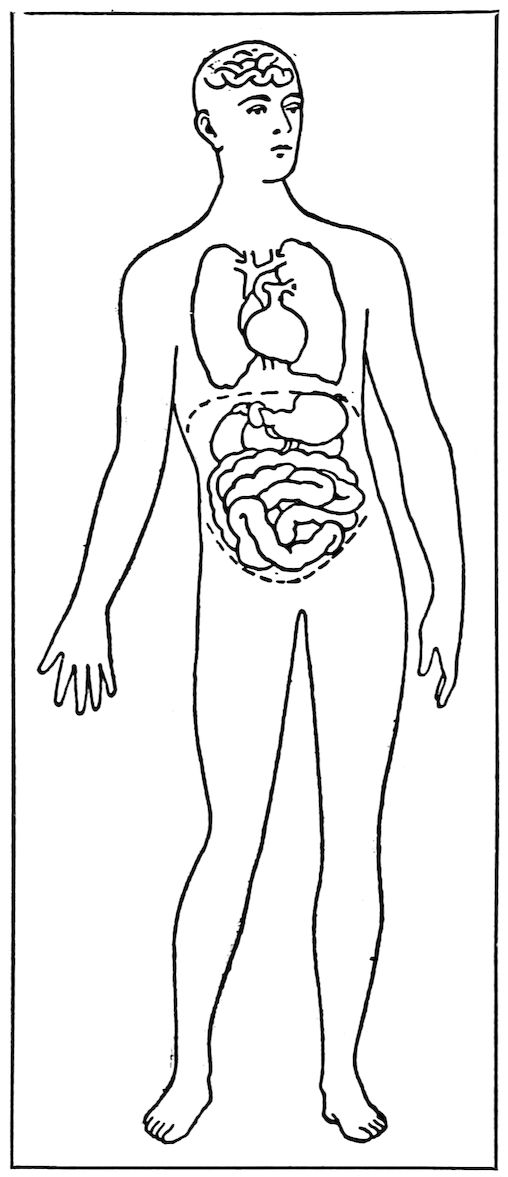

The Skull, Chest, and Abdomen.

In a general way, we may compare the human body to three closed boxes, one above another. These boxes are the skull, the chest, and the abdomen. Each one has its own special contents, formed to do a special work for the body. The skull is a hard, bony case made to contain the brain. This is where the mind lives, and it is part of the work of the mind to take care of the body and direct its movements. The brain maintains a sort of telegraph station within 9itself. Wires, which we call nerves, branch out from it to all parts of the body, and the brain is constantly receiving messages over these wires and sending others telling the muscles what to do. For instance, if the hand comes in contact with something hot, a message instantly goes to the brain, telling this fact. The brain sends back word to take the hand away, and the hand is withdrawn. But all this is done so quickly that the hand seems to be withdrawn the very instant that it comes in contact with the fire. The skull is supported by the backbone, which connects it with the second closed box.

This second cavity is the chest, which is really a sort of cage formed by the ribs, the backbone, and the breastbone. In the chest are the heart and the lungs. The heart is an engine. Put your hand over it and you can feel the steady throb of its beat, day and night. It is working all the time, whether you are awake or asleep. The business of the heart is to send blood to all 10parts of the body. It does this by driving the blood through tubes, called arteries and veins, that go all over the body. The arteries are deep down among the muscles, but some of the veins are close to the surface. We can see blue veins at the temples and on the backs of our hands. All the blood goes to every part of the body once in two minutes.

The third box, which we call the abdominal cavity, is separated from the chest by a broad, thin muscle, the diaphragm. The abdomen has a hard floor of bone, but the walls are soft, being made up only of the muscles and the lower ribs. In the abdomen are the stomach and intestines, the liver, 13kidneys, and other organs of which we shall learn later.